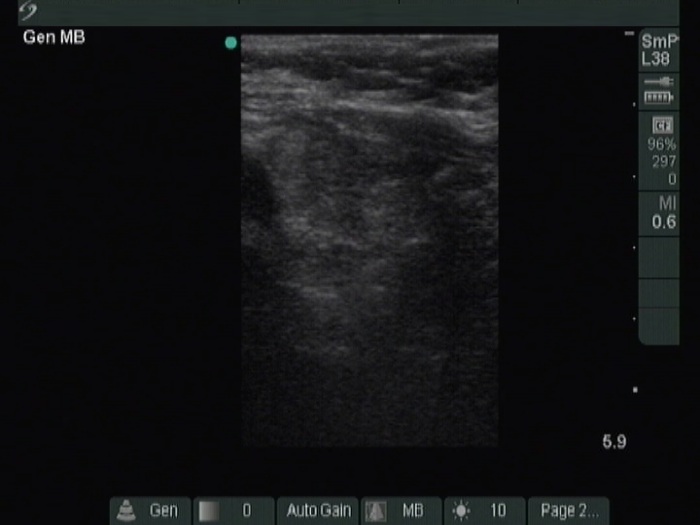

Thyroid cancers - case 1219 (ultrasonographic picture 8)

Left lobe, longitudinal view.